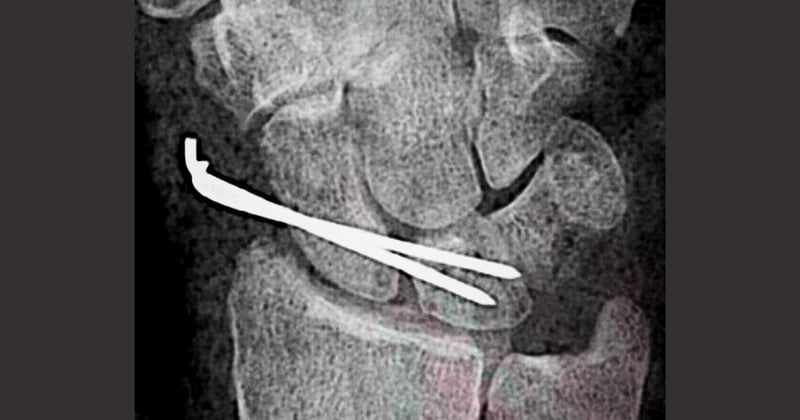

Fractura de radioFractura de radio

+1+1